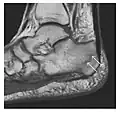

Figure 8: Proximal diaphyseal fatigue fracture of the tibia in a 20-year-old man with a history of regular jogging. (a) Lateral radiograph shows no obvious fracture lines but a subtle localized medial tibial cortex periosteal reaction (arrows). (b) Sagittal reformatted CT image acquired 1-month after the radiograph shows a linear hypoattenuation in the tibial cortex (arrowhead), as well as obvious periosteal thickening (arrows). (c) Sagittal T2-weighted fat-saturated image acquired the same day shows an area of hyperintensity spreading over the proximal tibia (arrows), which is consistent with the presence of proximal tibial fracture.[1]

Figure 9: Proximal metaphyseal fatigue fracture of the tibia in a 27-year-old recent male military recruit. (a) Anteroposterior radiograph is within normal limits. (b) Coronal T1-weighted MR image shows a marked linear hypoattenuation along the medial tibial metaphysis (arrow) surrounded by diffuse hypointensity in keeping with posttraumatic edema.[1]